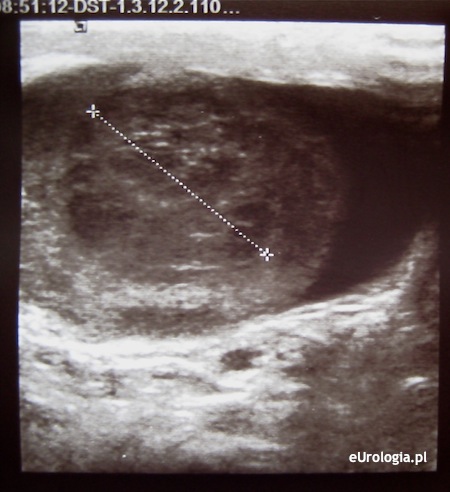

Mam powiększone jądro po lewej stronie. W badaniu USG wyszło, że w dolnym biegunie jądra jest niejednorodny obszar średnicy 20 mm z patologicznym unaczynieniem. Czy na podstawie badania USG wiadomo już, że mam raka jądra? Czy przy prawidłowych markerach można mieć raka jądra?

Rozpoznanie raka jądra stawiane jest na podstawie wyniku histopatologicznego preparatu z orchidektomii czyli po usunięciu jądra. Nieprawidłowy obraz ultrasonograficzny jądra może nasuwać podejrzenie raka. Konieczna jest pilna konsultacja urologiczna. Więcej informacji można znaleźć w dziale: Rak jądra - diagnostyka.

Fot. Nasieniak jądra - obraz USG